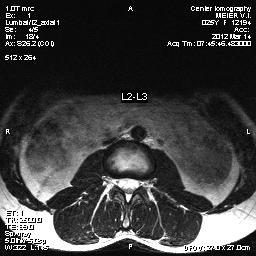

Интересует такой вопрос: почему при двух обследованиях МРТ получились разные показания (на одном мне поставили грыжу, на втором нет)

А вот это как раз иллюстрация того, что МРТ - не настолько точный метод, как принято думать. Чувствительный - да, но специфичность его низка. Почему на одном поставили грыжу, а на другом нет? Вариантов множество. Разный прибор. Разные врачи описывали (то, что один назовет грыжей, другой может и вообще не заметить). Может быть срез так прошел. Грыжа могла на самом деле исчезнуть (так бывает и весьма часто). Или на самом деле на одном снимке диск выступает чуть больше. Например, грыжа могла быть обнаружена на МРТ, которое вы сделали вечером, после того как целый день пробыли на ногах, а другое обследование могло быть сделано утром или после отдыха, когда диск восстановил свою форму (вы же слышали, что человек к вечеру ниже ростом?).

Не думайте, что если МРТ выявило грыжу, то грыжа эта обязательно есть у вас круглые сутки